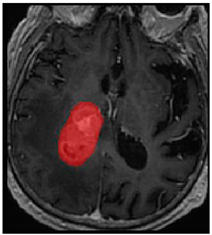

Three cases from the NTUH dataset showing representative results of different models were shown in Table 2, Table 3 and Table 4. The overall dice scores of these networks on the NTUH dataset ranged from 0.33 (DeepMedic) to 0.51 (V-Net). Table 5 shows the detailed performance of each network tested with the NTUH dataset.

Table 2.

Predictions with low dice scores.

Table 3.

Predictions with average dice scores.

Table 4.

Predictions with high dice scores.